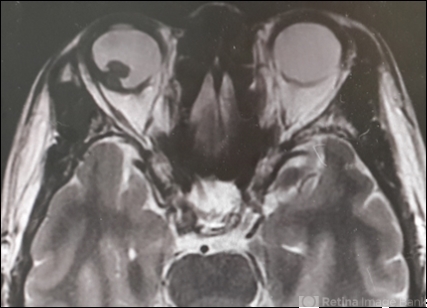

- chorioidal melanoma

- MRI

- MRI-W2 image of a 52-year-old man with a choriod melanoma.